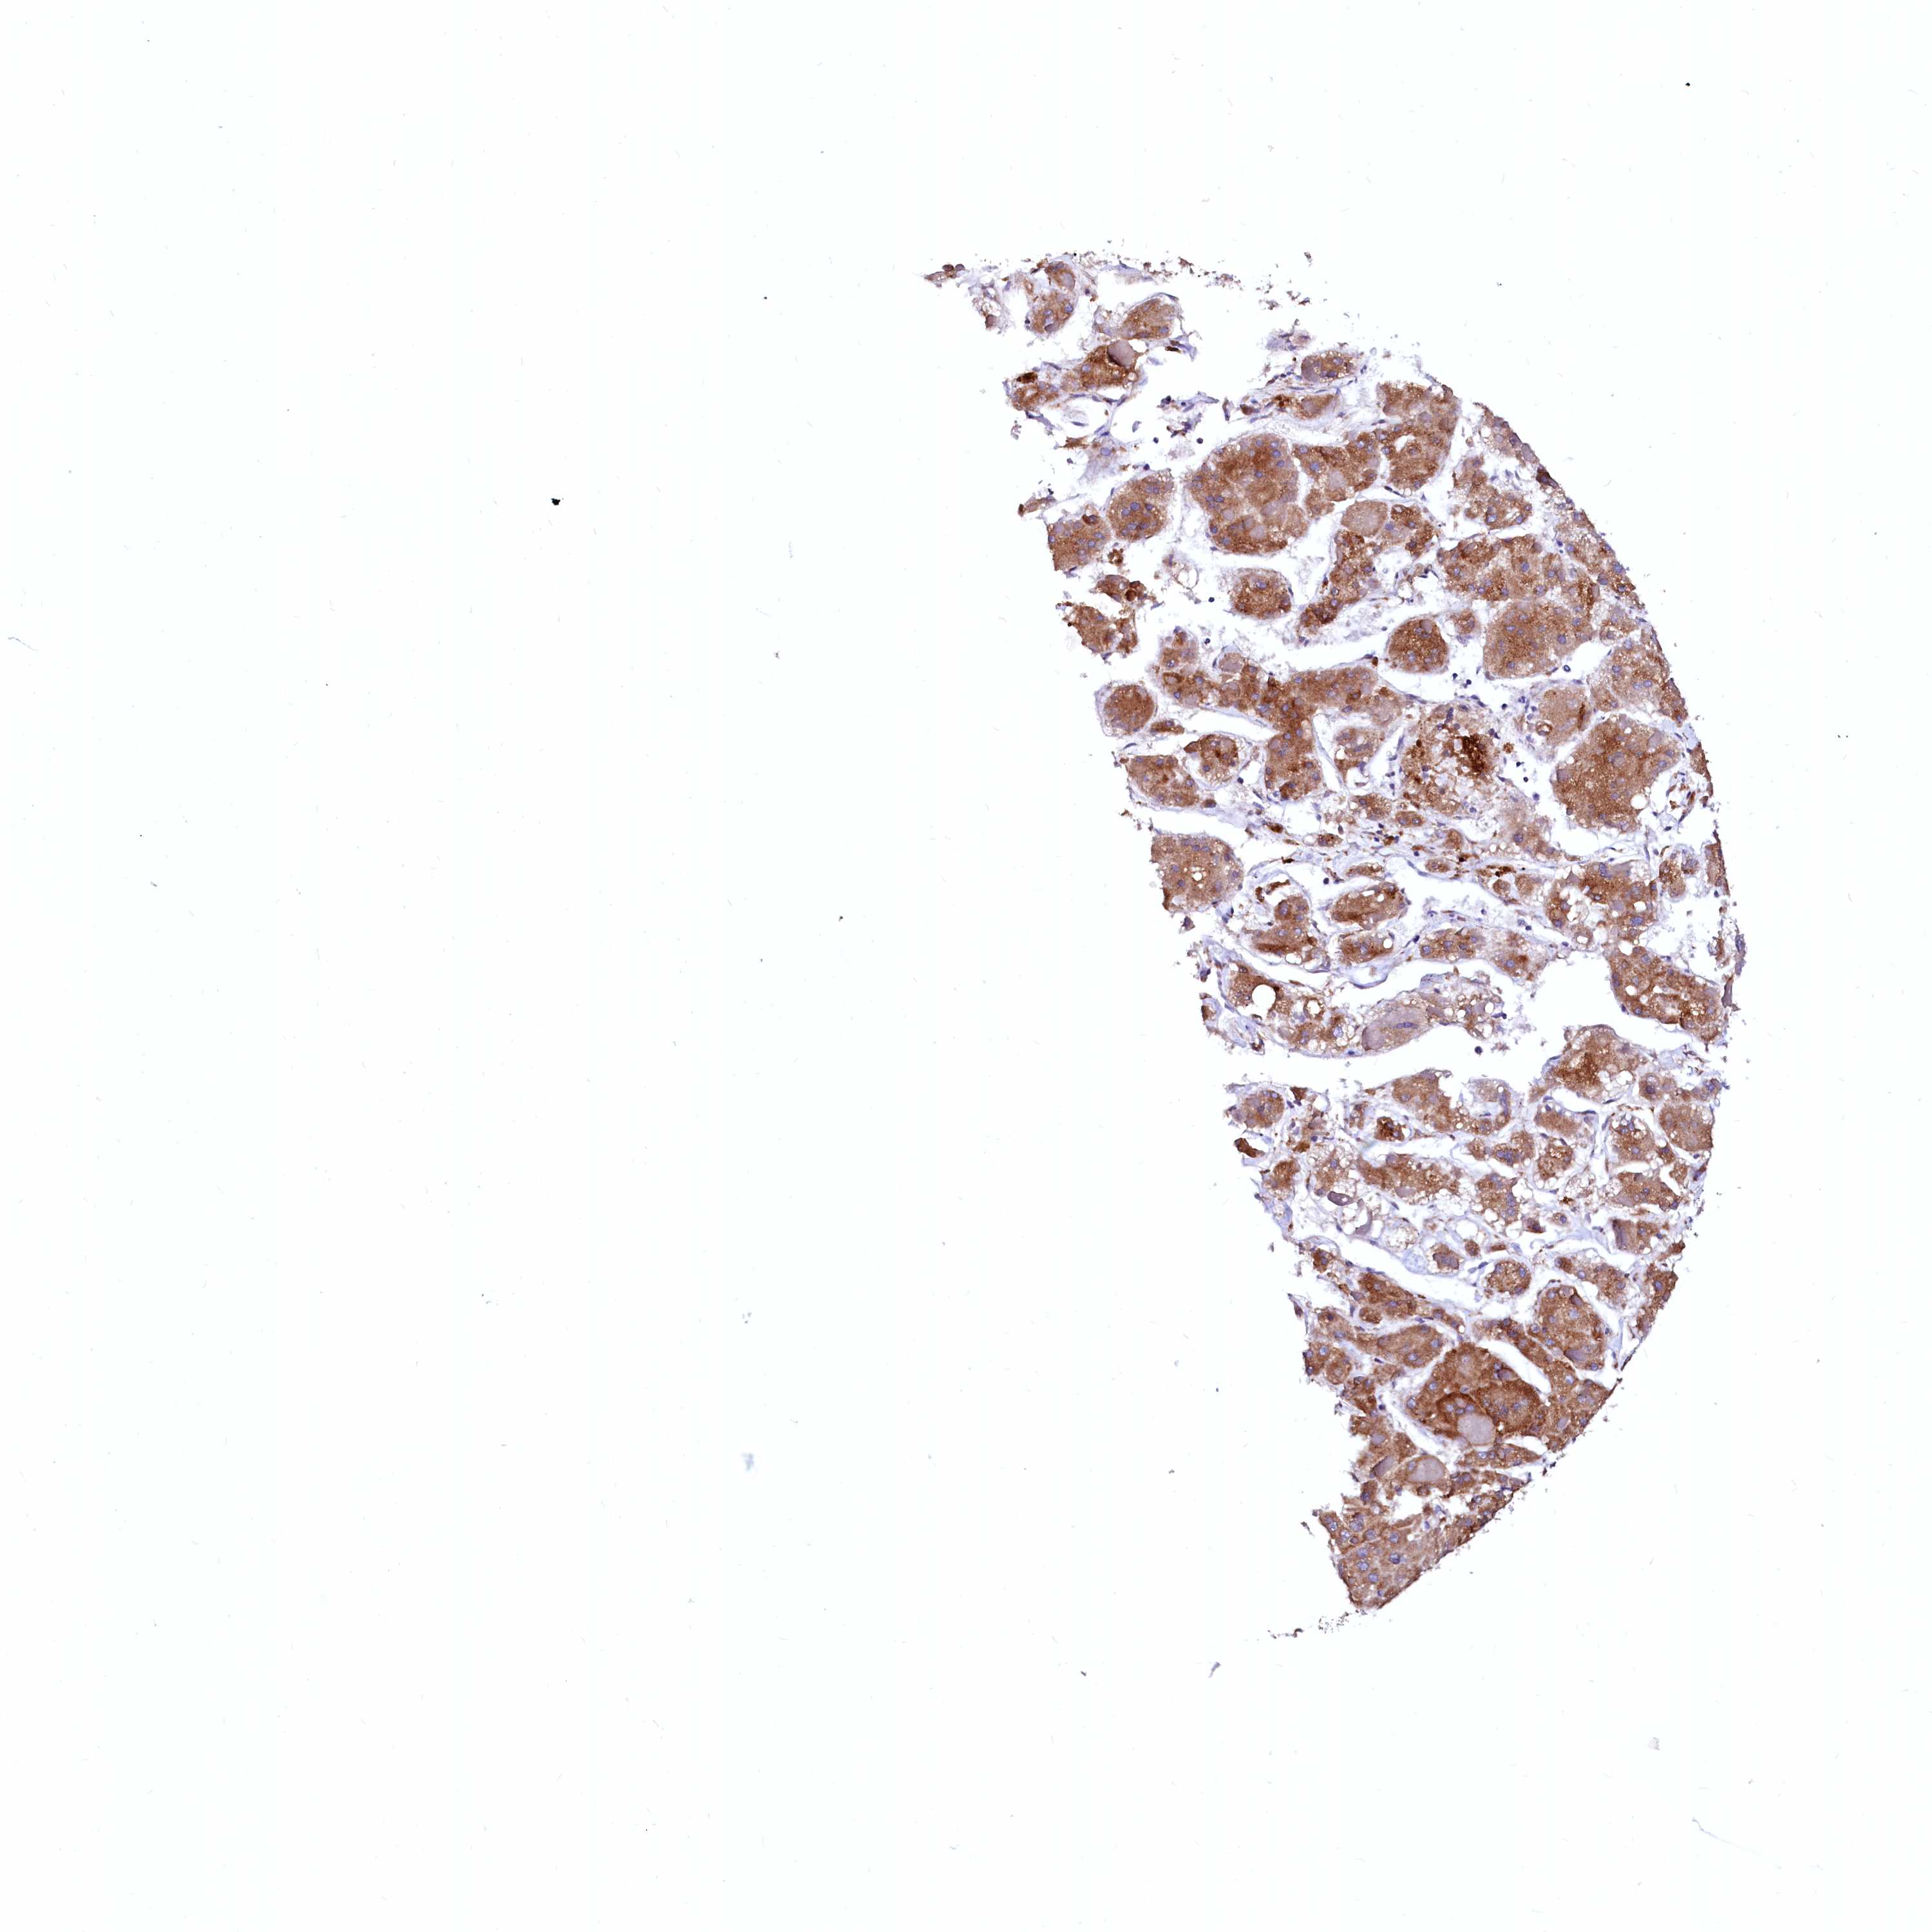

LIVER CANCER - Protein expressioni

A mouse-over function shows sample information and annotation data. Click on an image to view it in a full screen mode. Samples can be filtered based on level of antibody staining by selecting one or several of the following categories: high, medium, low and not detected. The assay and annotation is described here.

Note that samples used for immunohistochemistry by the Human Protein Atlas do not correspond to samples in the TCGA dataset.

Antibody stainingi

Antibody staining in the annotated cell types in the current human tissue is reported as not detected, low, medium, or high, based on conventional immunohistochemistry profiling in selected tissues. This score is based on the combination of the staining intensity and fraction of stained cells.

Each image is clickable and will lead to virtual microscopy that enables deeper exploration of all samples and also displays staining intensity scores, fraction scores and subcellular localization as well as patient and tissue information for each sample.

Antibody HPA002320

Antibody CAB037163

Staining

High

Medium

Low

Not detected

Intensity

Strong

Moderate

Weak

Negative

Quantity

>75%

75%-25%

<25%

None

Location

Nuclear

Cytoplasmic/membranous

Cytoplasmic/membranous,nuclear

Cholangiocarcinoma

Carcinoma, Hepatocellular, NOS